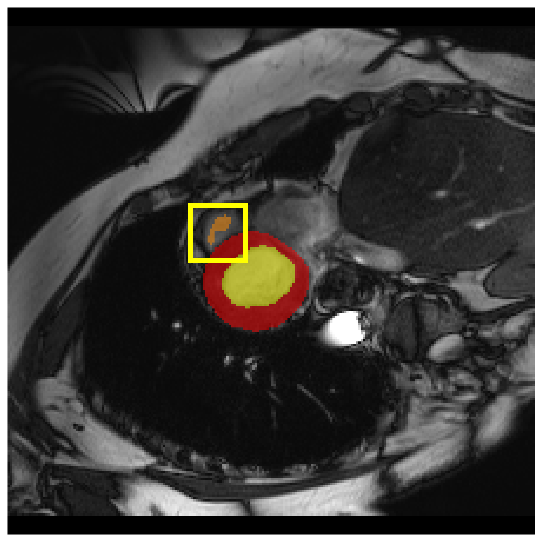

4.3.2 Visual Comparisons

Visualization of our method on the Synapse and ACDC datasets is shown in Fig. 3(a) and Fig. 3(b). For the Synapse dataset illustrated in Fig. 3(a), FCT failed to accurately segment SM and GB, while MERIT achieved precise segmentation of SM but struggled with GB. In contrast, our method achieved accurate segmentation of both SM and GB. Regarding the ACDC dataset shown in Fig. 3(b), while previous methods achieve comparable segmentation of the Myo and LV to the GT, they exhibit noticeable errors on the RV, including invasion into adjacent organs and misrecognition. On the other hand, our method accurately segments across all three structures Myo, LV, and RV, performing as precisely as the GT. We demonstrate the superiority of our method quantitatively and qualitatively.